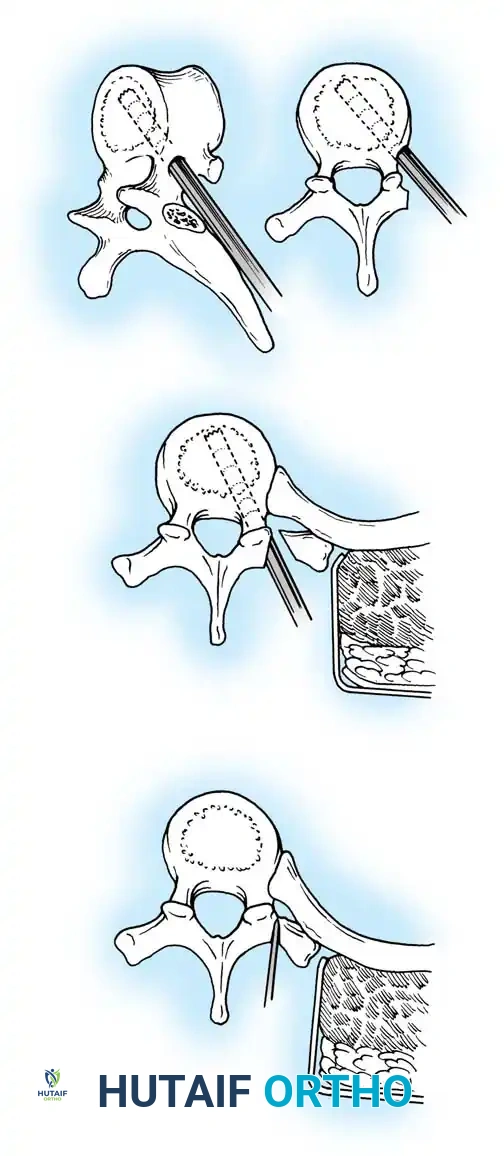

Fig. 38-201: Surgical diagrams illustrating pedicle preparation and instrumentation strategies in dystrophic vertebrae.

Segmental pedicle screw systems provide superior biomechanical purchase in dysplastic bone, permitting early ambulation. However, the fusion mass in NF-1 is notoriously unreliable. If the instrumentation purchase is tenuous, postoperative bracing is mandatory. Furthermore, the fusion mass must be scrutinized at 1 year postoperatively; if progression exceeds 10 degrees or pseudarthrosis is suspected, the mass must be re-explored and augmented with robust autogenous iliac crest bone grafting.